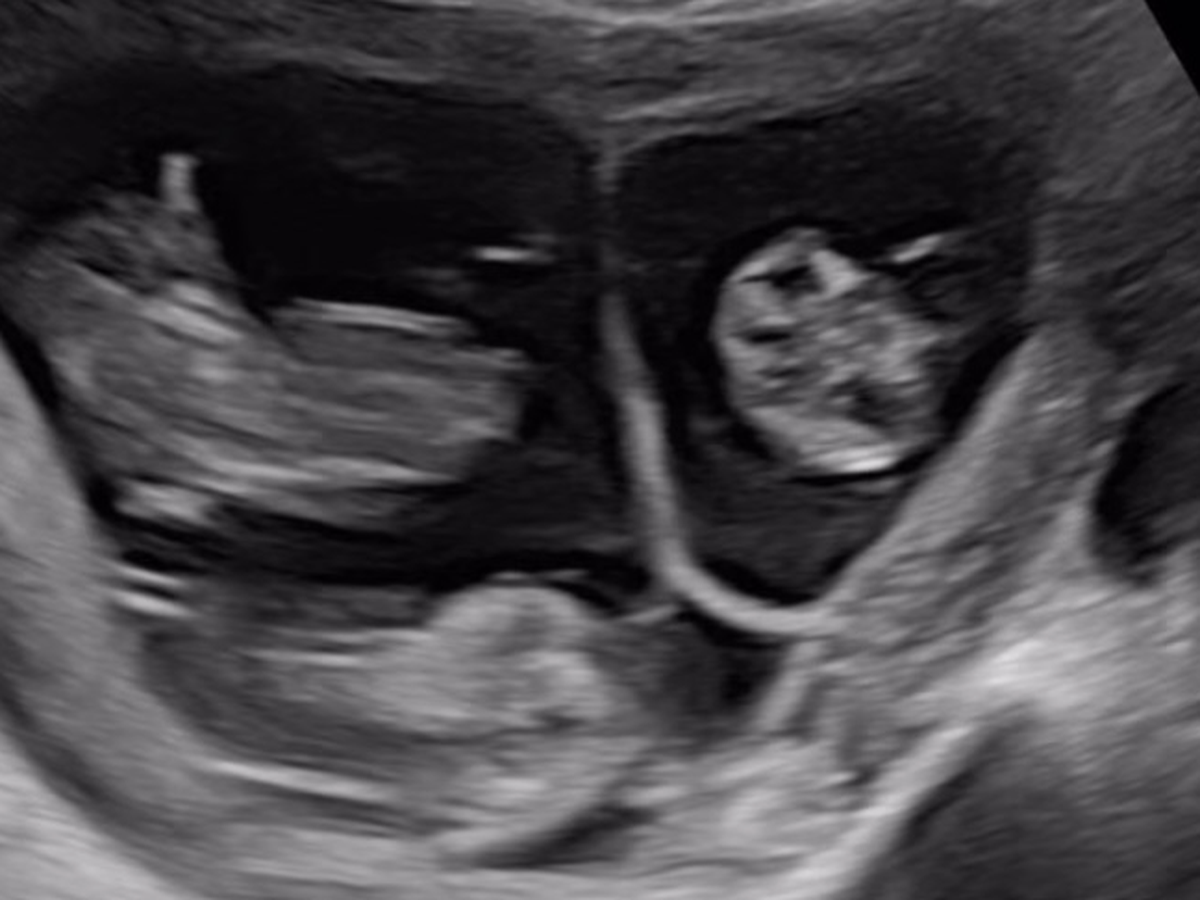

Lucy and Ana are having triplets! After their marriage in 2021, they worked hard to develop the financial stability to start a family. They felt ready in 2024, did their research on reputable sperm banks in their area, and put the plan in motion with their first ICI in January 2025. Then, a chaotic miracle happened... Lucy got a positive test after their first ever try! She scheduled her first appointment, where she found out they are pregnant with TRIPLETS! Not to mention that they hadn't used any fertility treatments at all to increase their chances of conception or having multiples. The chances of triplets occurring in this way, especially without a family history of multiples is about one in 10,000 pregnancies.

And that's not all. Triplet pregnancies come with a lot of risks. While each baby has their own amniotic sack, babies B and C share a placenta, which increases the risk of uneven nutrient sharing. Lucy is also at a higher risk for gestational diabetes and pre-eclampsia. The triplets are currently measuring mostly equally, which is fantastic news that hopefully continues as they grow! The doctors anticipate the babies arriving pretty early, anywhere from 28 to 32 weeks gestation. That puts us around late July or early August (meaning they’ll either have 3 more Cancers, or 3 Leos to raise...) to get everything as ready as possible.